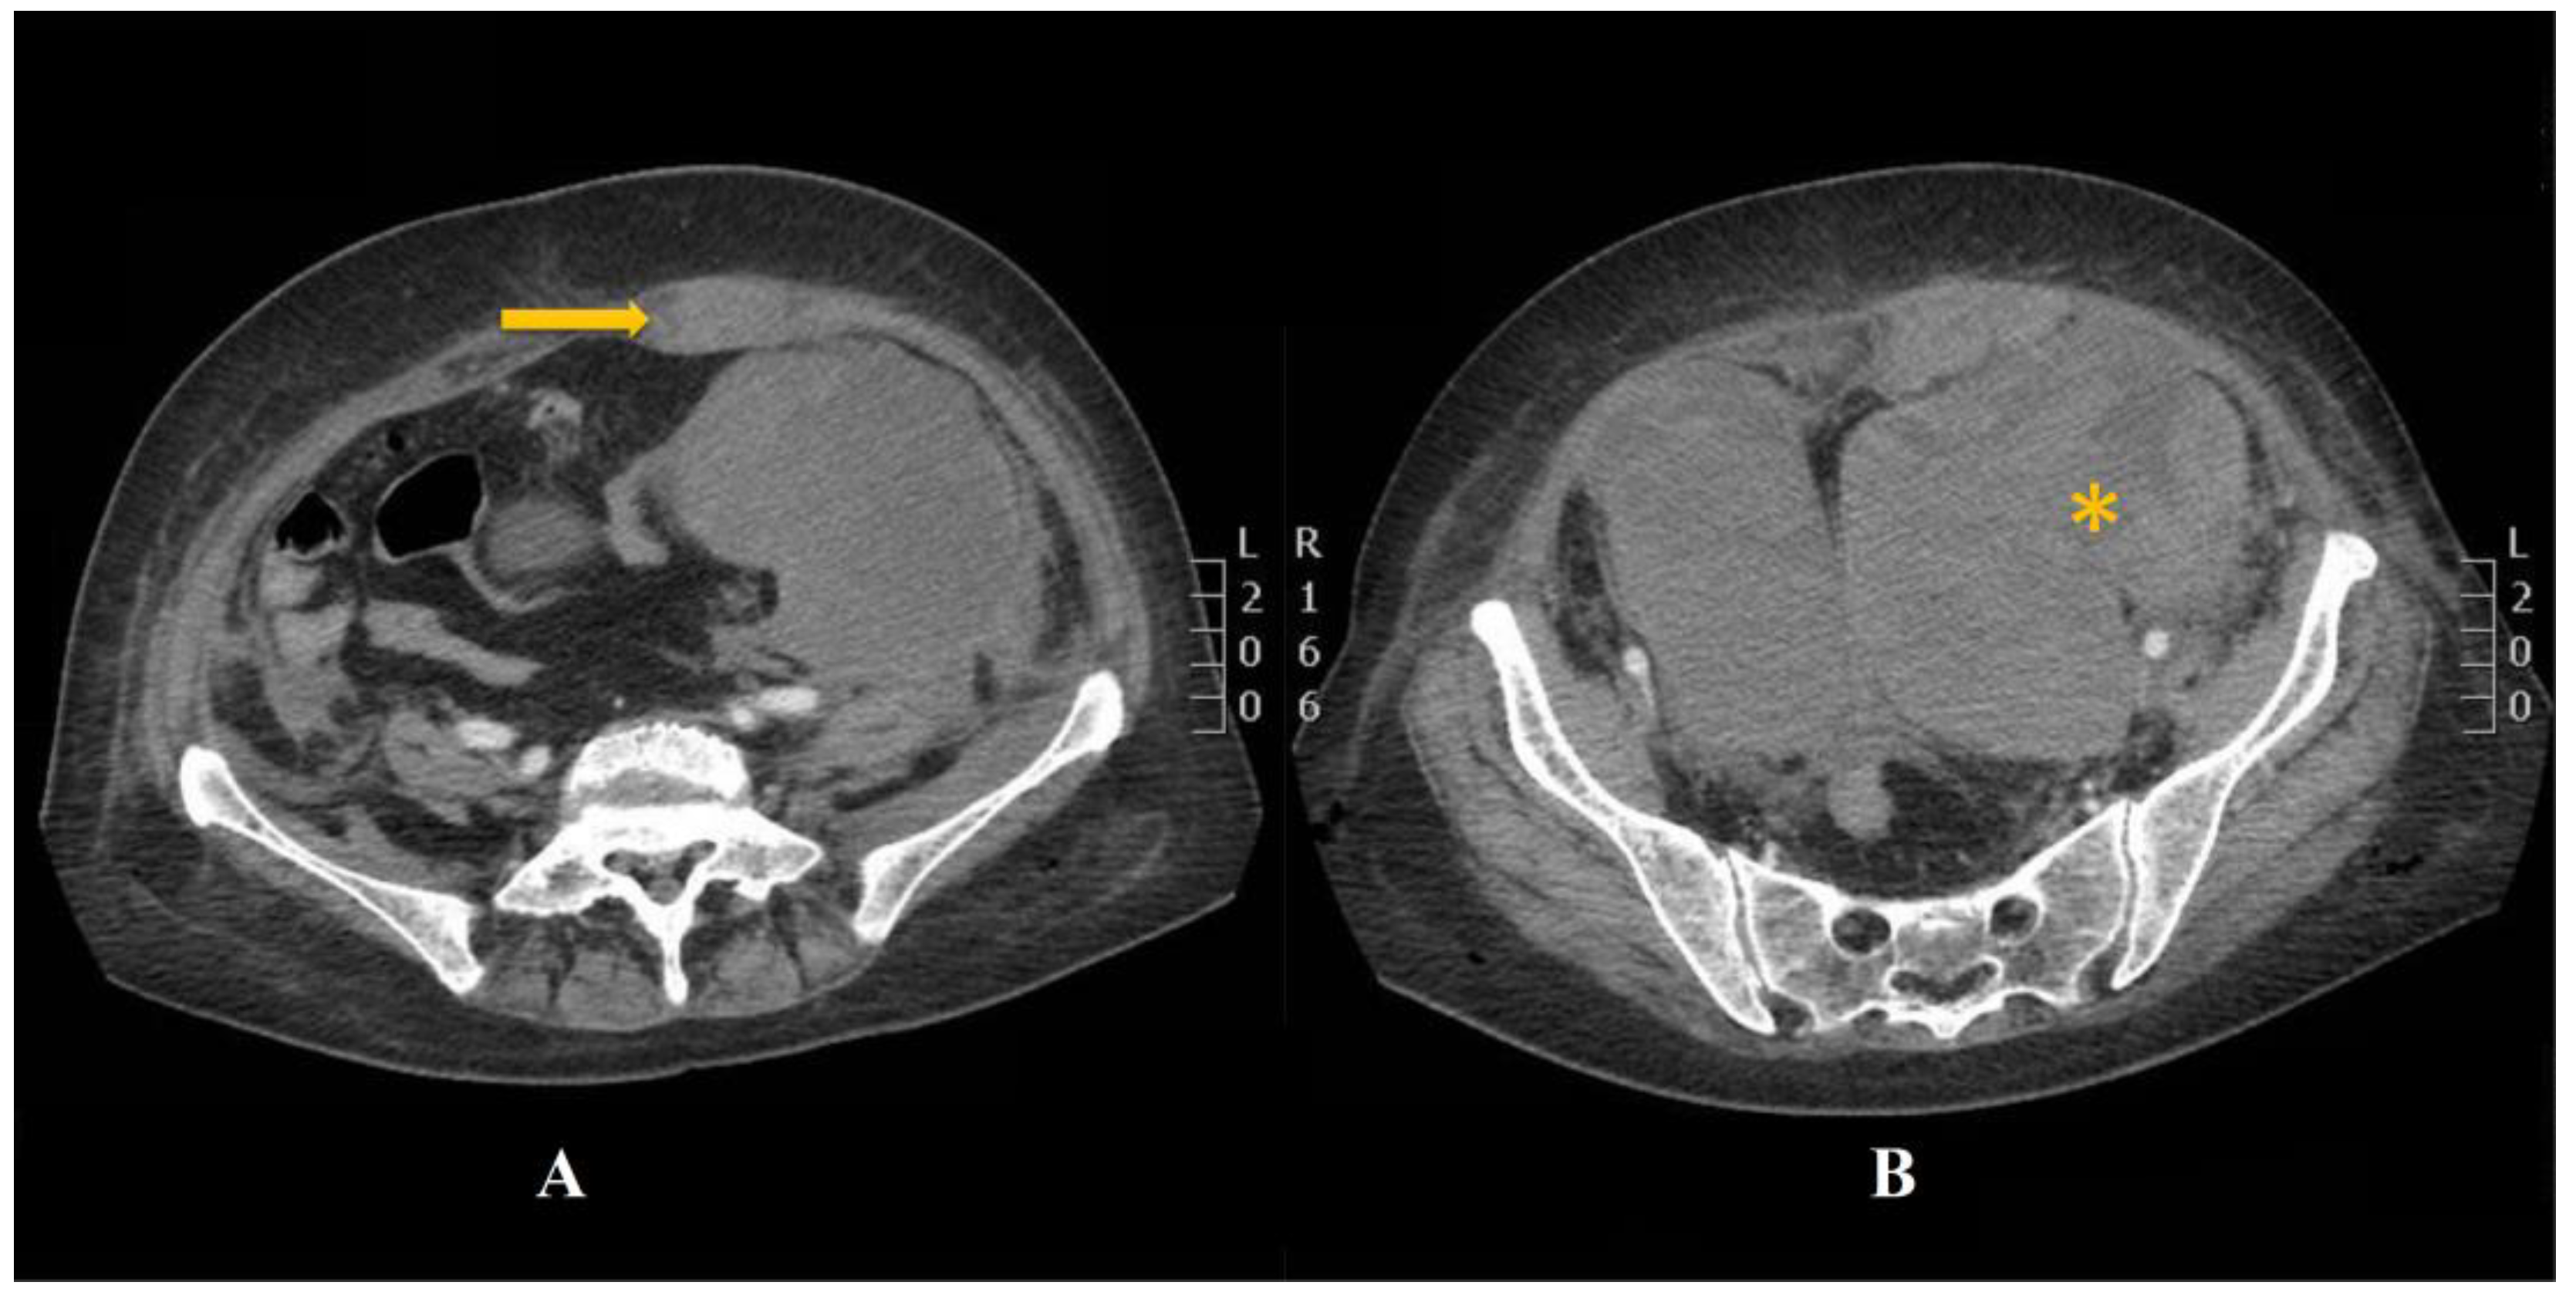

2. Case Presentation

2.3. CT Scan Report